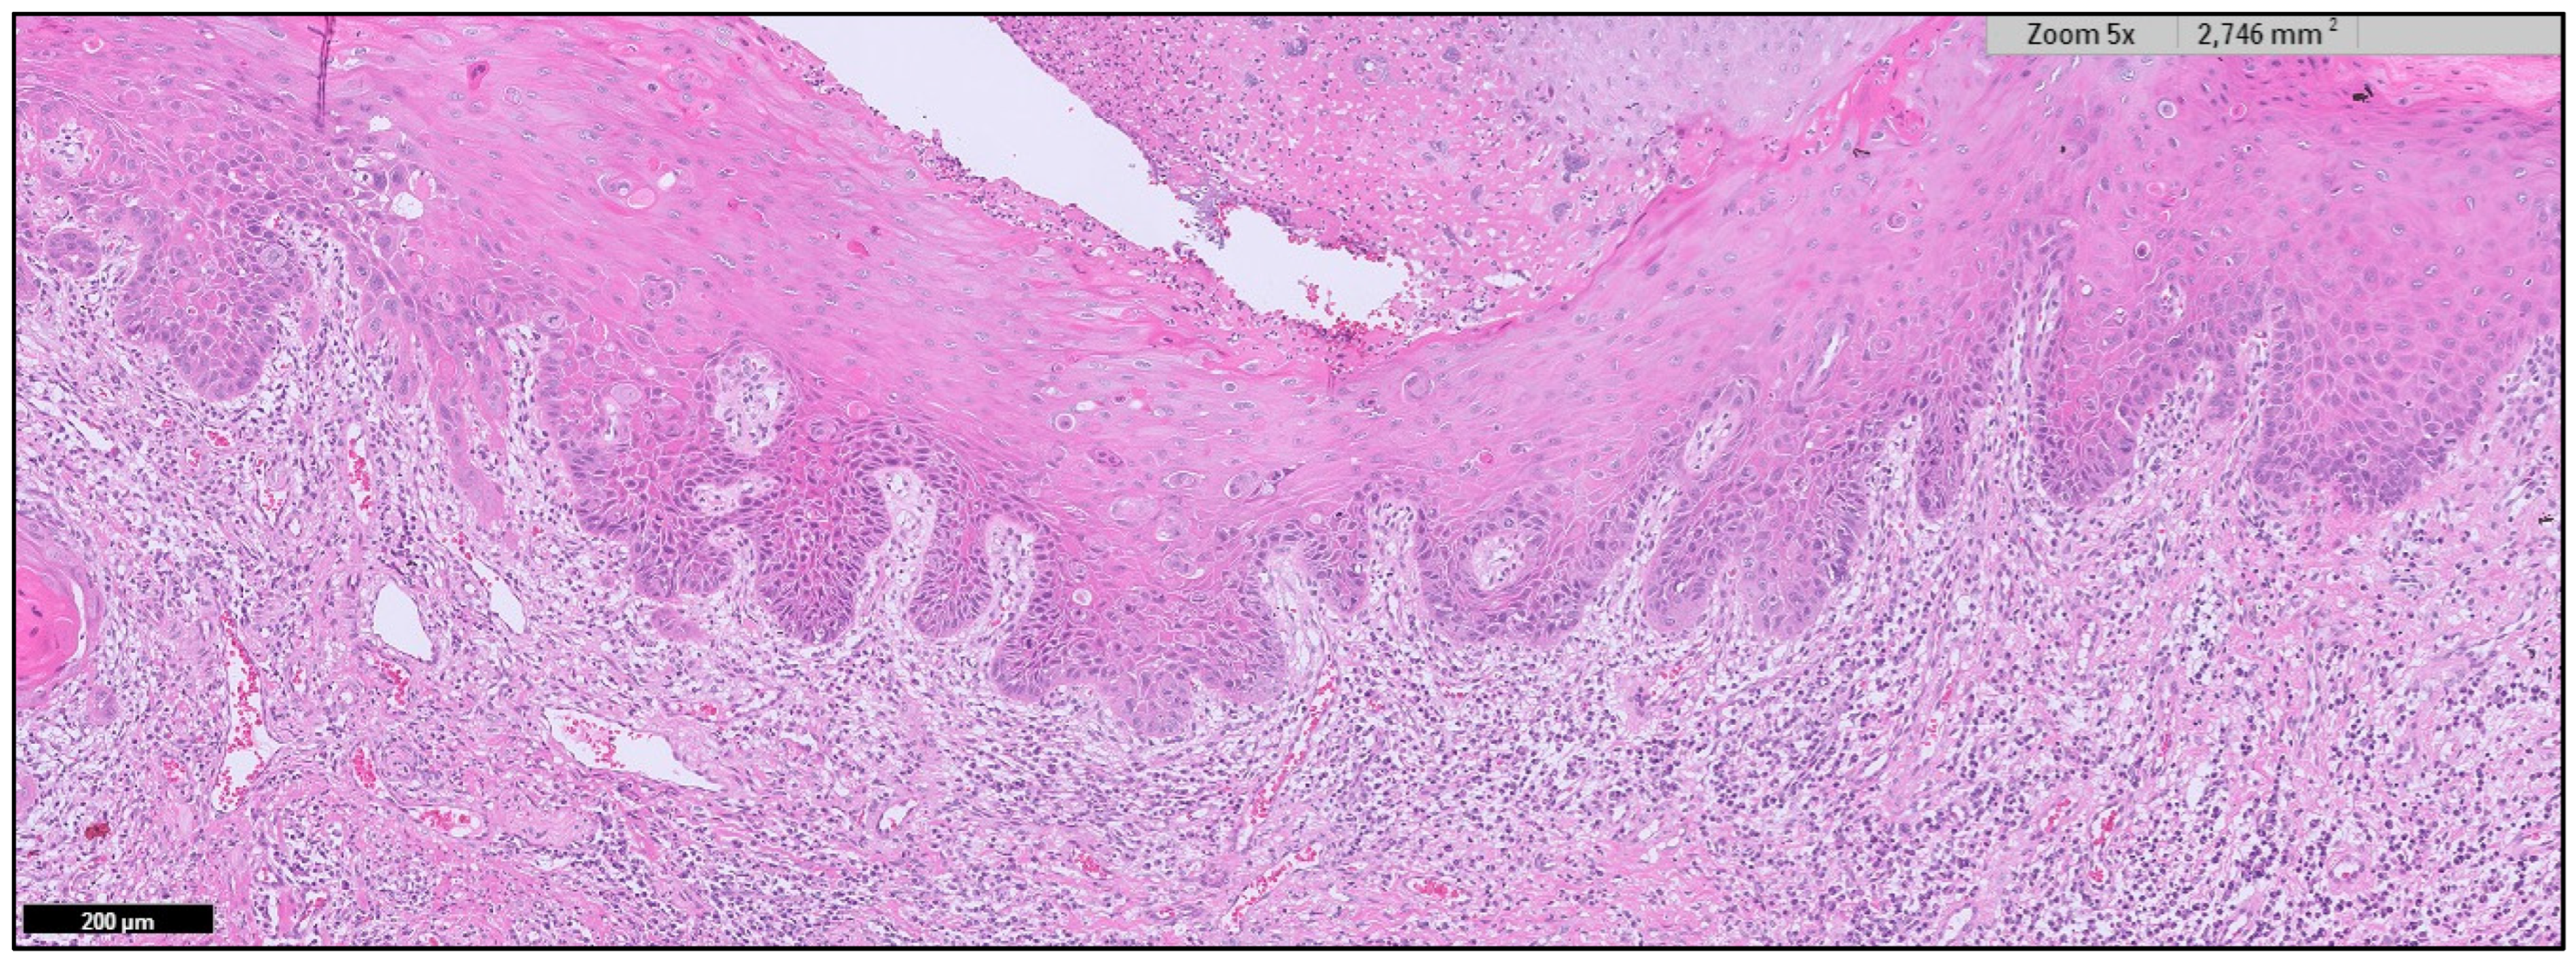

Appendix A. Clinical Presentation of OPMD

General Principles of Treatment of the Main OPMDs

- Odell, E.; Kujan, O.; Warnakulasuriya, S.; Sloan, P. Oral epithelial dysplasia: Recognition, grading and clinical significance. Oral Dis. 2021, 27, 1947–1976. [Google Scholar] [CrossRef]